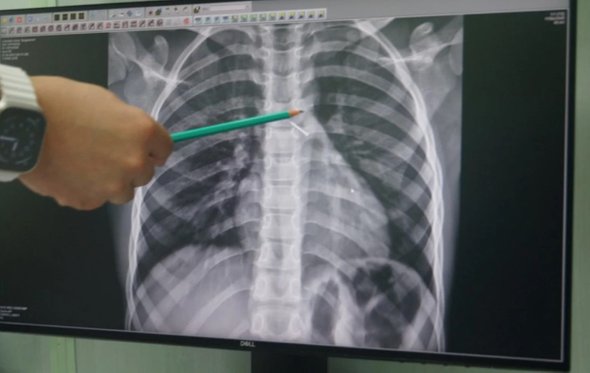

«Обследование показало, что канцелярская кнопка попала в бронхи, уперлась в одну из стенок и вызывала локальное воспаление. Заведующая эндоскопическим отделением Ольга Ахалкалакелова рассказала, что опасный предмет успешно достали с помощью эндоскопических зажимов», — добавили в пресс-службе минздрава.

фото: минздрав Новосибирской области